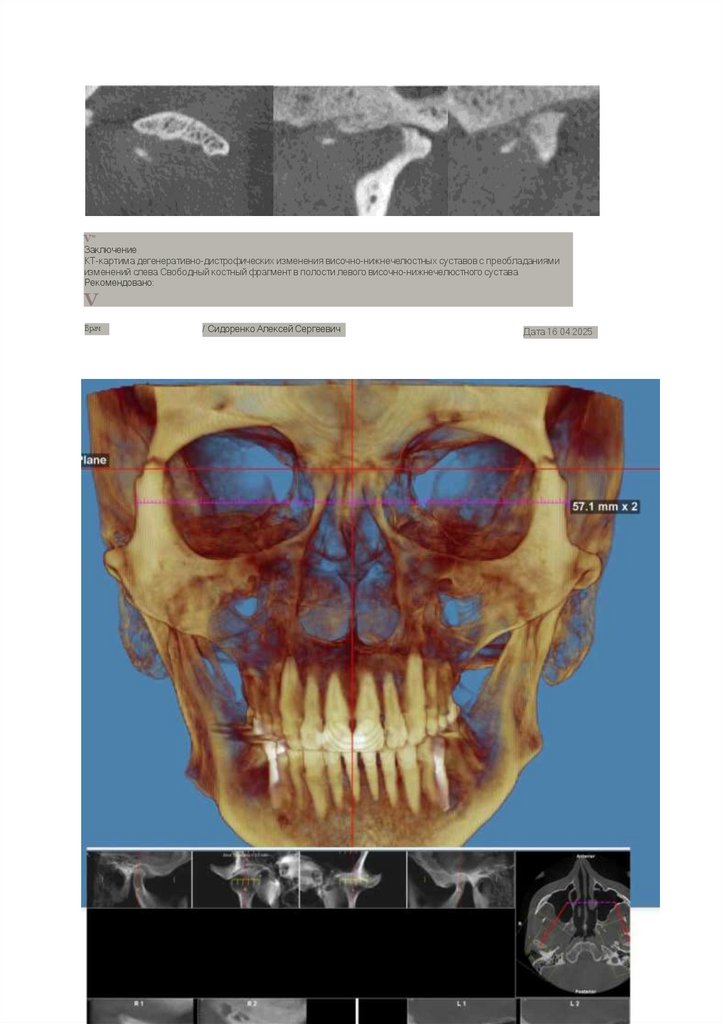

V*

Заключение

КТ-картима дегенеративно-дистрофических изменения височно-нижнечелюстных суставов с преобладаниями

изменений слева Свободный костный фрагмент в полости левого височно-нижнечелюстного сустава

Рекомендовано:

V

Врач

/ Сидоренко Алексей Сергеевич

Дата 16 04 2025